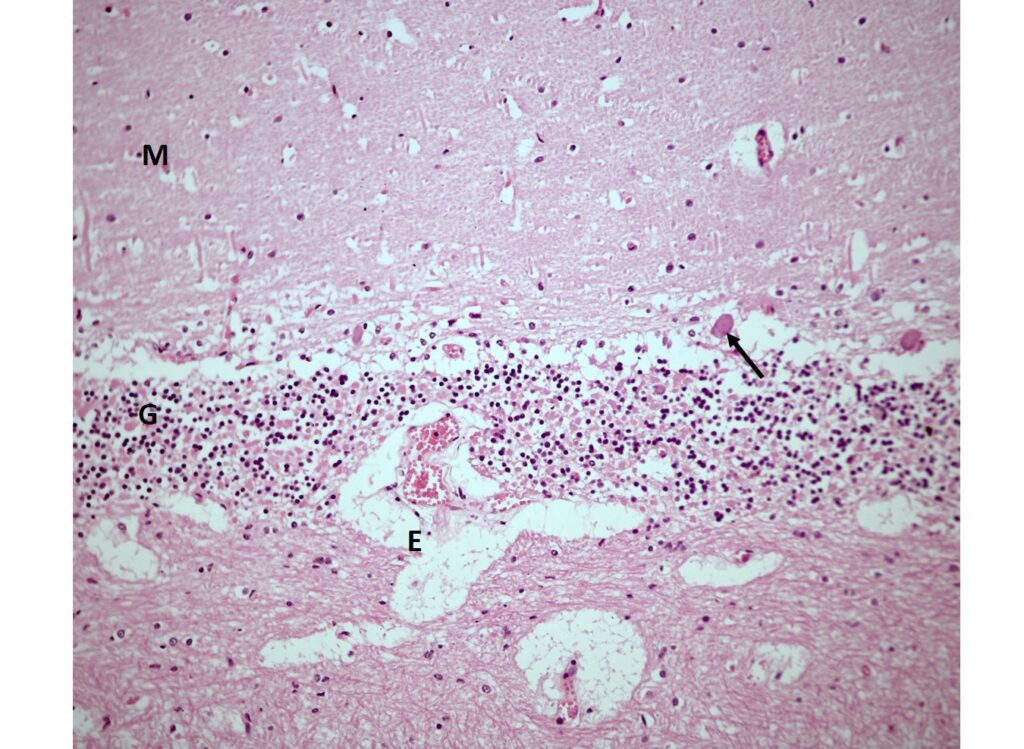

Šestiměsíční samice lva berberského (Panthera leo leo) byla ošetřena kvůli přetrvávající ataxii. Výsledky hematologického a biochemického vyšetření krve byly v mezích normy, s výjimkou nálezu zvýšeného hematokritu, zvýšené hladiny albuminu, zvýšené aktivity CPK, hyperglykémie a mírné hyperkalcémie. Hladina vitamínu A v séru tohoto lvíčete byla výrazně nízká (44 µg/l) v porovnání s hodnotami publikovanými pro zdravé lvy. Po suplementaci vitamínem A nedošlo ke zlepšení, a naopak se dostavily head tilt, hypermetrie a stargazing. Proto bylo provedeno MRI vyšetření mozku a krční míchy. Vyšetření odhalilo výrazné zbytnění týlní kosti a tentoria cerebelli, kompresi a herniaci mozečku, kompresi prodloužené míchy a těžkou syringo/hydromyelii krční míchy. Byly zjištěny kostní změny odpovídající hyperostóze lebky a vzhledem k ireverzibilním změnám bylo lvíče utraceno. Histologicky byla diagnostikována tlaková atrofie mozečku s úbytkem Purkyňových buněk a degenerativní myelopatií. Kostní malformace lebky u mladých lvů chovaných v zajetí jsou považovány za důsledek hypovitaminózy A v souvislosti s krmením svalovinou, tedy potravou bez obsahu vnitřností, které jsou přirozeným zdrojem vitamínu A.

A six-month-old female Barbary lion (Panthera leo leo) was treated for persistent ataxia. Hematological and biochemical examinations were within normal limits, except for elevated hematocrit, increased albumin levels, elevated CPK activity, hyperglycemia, and mild hypercalcemia. The serum vitamin A level in this cub was markedly low (44 µg/l) compared to values reported in healthy lions. Since no improvement was observed after vitamin A supplementation and new symptoms such as head tilt, hypermetria, and stargazing appeared, MRI of the brain and cervical spinal cord was performed. The examination revealed marked thickening of the occipital bone and tentorium cerebelli, compression and herniation of the cerebellum, compression of the medulla oblongata, and severe syringo-/hydromyelia of the cervical spinal cord. The cub exhibited bony changes consistent with calvarial hyperostosis and was euthanized due to irreversible neurological damage. Histopatological examination revealed compressive cerebellar atrophy with loss of Purkinje cells and degenerative myelopathy. Cranial bone malformations in captive lions are considered to result from vitamin A deficiency. This deficiency has been described only in young lions fed exclusively on red meat without organ tissues, which are the natural source of vitamin A.*